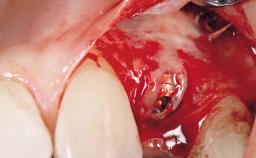

Treatment of Peri-Implant Mucositis at a Zirconia Implant

Frank Schwarz, Ausra Ramanauskaite

Recent clinical studies, most with short-to-medium term observation periods, have reported on the favorable clinical performance of zirconia implants in terms of survival rates, clinical, and radiographic outcomes (Roehling and coworkers 2016; Roehling and coworkers 2017; Rodriguez and coworkers 2018; Lorenz and coworkers 2019). Nonetheless, a rather high incidence of peri-implant disease at zirconia implants (39% of implants) was noted throughout a two-year period, highlighting the need for treatment protocols of peri-implant diseases at zirconia implants (Becker and coworkers 2017).